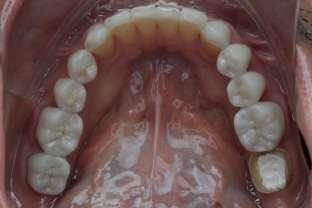

Si presenta alla nostra attenzione un paziente maschio, 35 anni, in apparente salute sistemica, fumatore, con la richiesta di controllare delle white spots, una leggera sensibilità e la richiesta di migliorare la luminosità del suo sorriso. Viene compilato e firmato il consenso informato. Il paziente viene motivato ad più efficace controllo del biofilm batterico e attraverso la condivisione dell’immagine clinica della topografia del biofilm batterico, (T.B.M.) scegliamo lo scovolino in gomma GUM Soft-picks (Sunstar) e lo sollecitiamo all’uso efficace degli spazi sovracrestali e allo spazzolamento in maniera delicata ma efficace della lingua. Sottoponiamo il paziente alla terapia parodontale non chirurgica con ablatore Comby touch (MECTRON) in modalità soft-mode per contenere la sua sensibilità. Valutiamo la sensibilità e modifichiamo i suoi stili di vita di igiene orale, di igiene alimentare e chiediamo di smettere di fumare. Il paziente riferisce di non essere disposto a rinunciare al fumo e chiediamo di ridurre il rischio di patologie e di discromie

da tabagismo passando all’uso dei dispositivi a tabacco riscaldato. Successivamente rileviamo il colore, con spettrofotometro, e con scala-colori Vita e documentiamo fotograficamente la condizione clinica presente.

Il colore rilevato è A2. Sottoponiamo il paziente ad uno sbiancamento pro-

fessionale con un principio attivo PAP (acido ftalimidoperossicaproico) che presenta il vantaggio di non sollecitare la sensibilità, pur mantenendo l’aspettativa di un risultato efficace nell’ottenere la luminosità del sorriso. Lo sbiancante ad uso professionale BRILLIANT LUMINA (Coltene), risulta essere per l’operatore di facile applicazione: ven-

gono protette le gengive con la diga liquida fotopolimerizzata, e si mescola il gel sbiancante lasciando cadere nel vasetto contenente 2 ml di gel, 3 gocce di liquido attivatore. Si ottiene il gel sbiancante di una consistenza ideale per una applicazione sulle superfici dentali sicura e pratica durante l’apposizione. Vengono eseguiti 4 step da 15 minuti.

Dopo ogni step viene aspirato il gel, pulite le superfici dentali con del cotone idrofilo e si riappone nuovamente il gel. Al termine dei 4 step, si aspira, si asciuga e viene tolta la diga. Si rileva e si condivide con il paziente il risultato ottenuto, A1, e viene documentato fotograficamente. Il paziente appare gioioso del risultato è favorevolmente colpito di non aver sofferto durante il trattamento di sensibilità. Alla persona assistita sono stati programmati dei follow-up per il trattamento successivo delle white spots con applicazioni di resine infiltranti e rigenerazione guidata dello smalto.